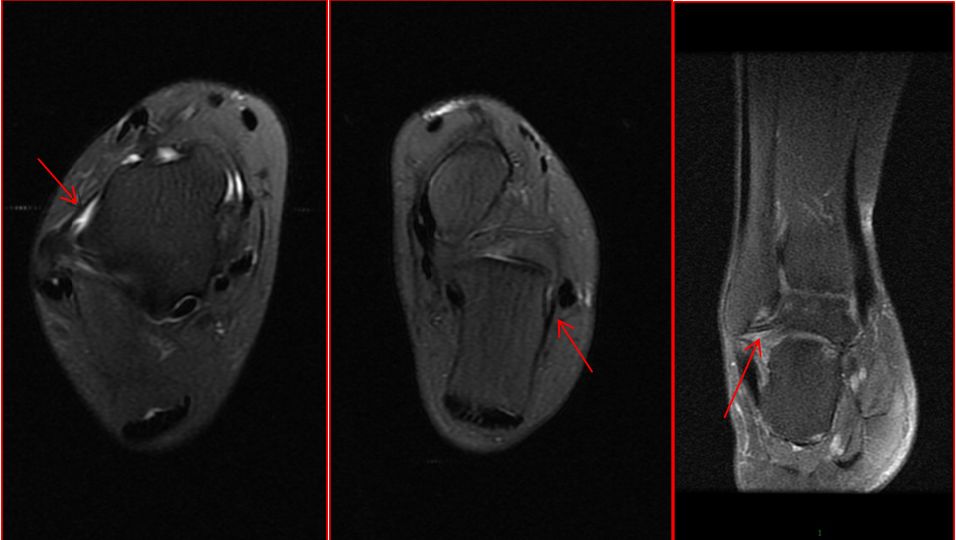

以上依次为距腓前韧带、跟腓韧带、距腓后韧带正常核磁表现